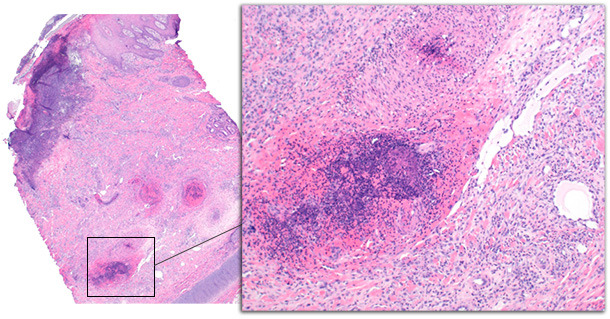

L’histopathologie de l’épiderme et du derme des porcs avec affection aigüe a montré une inflammation péri vasculaire de la couche profonde du derme avec des changements minimes de l’épiderme (figure 2). Les changements de l’épiderme comprenaient de l’acanthose et de l’hyperkératose orthokératosique. Sur un cas, les éosinophiles prédominaient, avec de la vascularite, de la thrombose et de la nécrose épidermique. Les changements sur les porcs atteints chroniquement comprenaient une ulcération, de l’acanthose irrégulière, une formation de tissus de granulation et une thrombose sur les couches profondes du derme (figure 3). Les changements chroniques sont semblables à ceux décrits précédemment (Jensen 2009, Richardson, Morter et al. 1984)

Figure 3 – Biopsie de la pointe de l’oreille d’un porc avec une affection chronique. Les changements épidermiques comprennent une ulcération avec une inflammation sous-jacente, la formation d’une croûte séro-cellulaire et de l’acanthose de l’épiderme. Les vaisseaux du derme profond sont atteints par de la thrombose et de la vascularite.